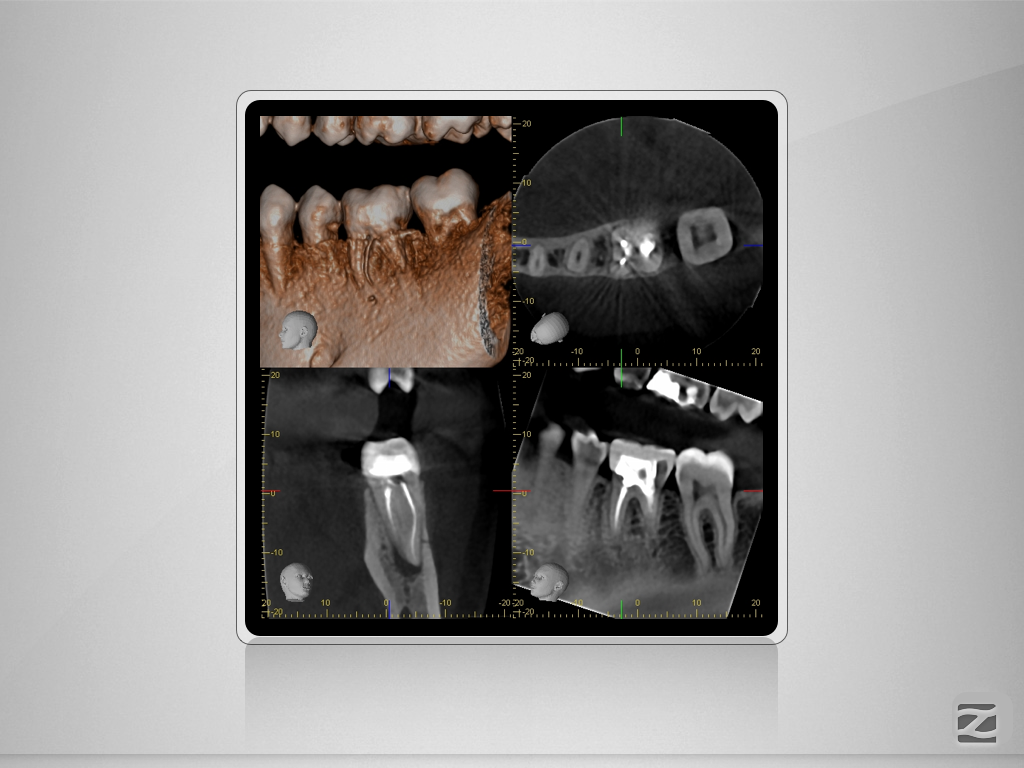

36D.004

Fraktur auf voller Arbeitslänge